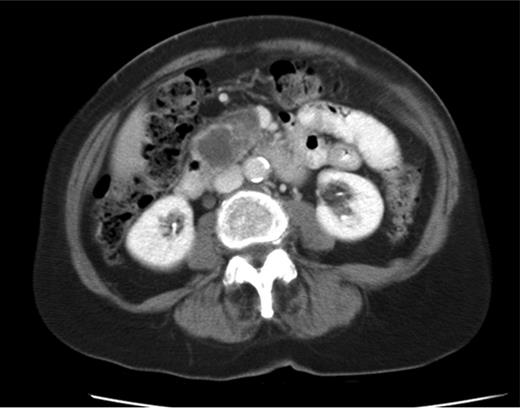

Following the histological findings, a CT of her thorax, abdomen and pelvis was arranged (Fig. 2). The CT scan reported a large solid cystic mass in the uncinate process of the pancreas measuring 7.2 cm × 4.8 cm in the axial dimension and 7.2 cm in the coronal dimension (Fig. 3). There was displacement of the superior mesenteric vein and artery but no vascular invasion. The CT scan also confirmed lung lesions consistent with metastatic disease (Fig. 3b and c).

(a) CT image of 2015, a mass lesion in the head of the pancreas with solid and cystic components (bunch of grapes appearance). The lesion measures 7.2 × 4.8 cm in the axial dimension and 7.2 cm in the coronal dimension. (b and c) Multiple focal ground-glass density nodules in both upper lobes of the lungs, largest measuring 1 cm in the right upper lobe.